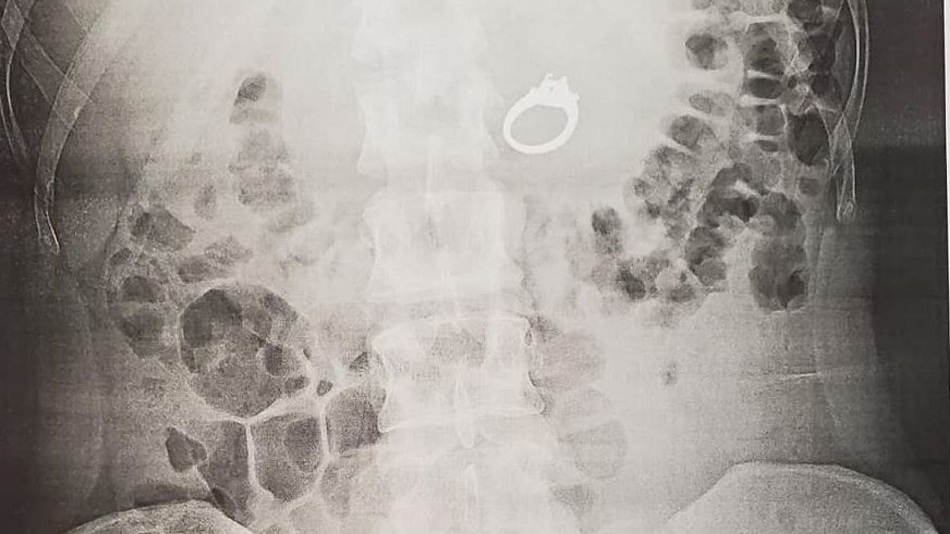

Elle s’est ensuite rendue dans une clinique pour un soin d’urgence. « Le médecin a ordonné une radiographie et semblait assez choqué quand elle est revenue avec un deuxième médecin et m’a montré que, bien sûr, ma bague était juste dans mon estomac ! » a-t-elle déclaré. Jenna a finalement dû subir une endoscopie supérieure pour retirer la bague en diamant de 2,4 carats. « Les médecins ont donné la bague à Bobby et il a par la suite rendu ma bague » a-t-elle déclaré.